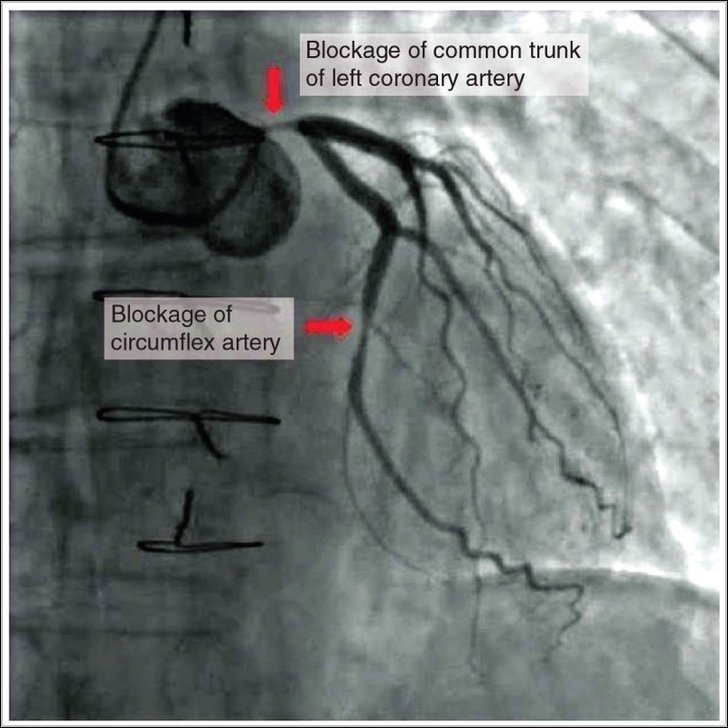

Occluded coronary arteries from atherosclerotic plaque rupture and thrombosis deprive downstream myocardium of oxygen, causing ischemia then infarction if prolonged, with left anterior descending affecting large anterior wall, right coronary inferior and right ventricle, circumflex lateral, manifesting as crushing chest pain, ECG changes, troponin rise, treated urgently with reperfusion via PCI or thrombolysis to salvage tissue.

Occluded Coronay Arteries